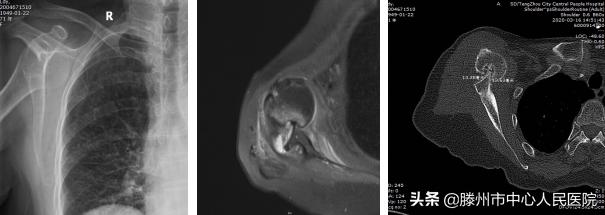

患者术前检查:右肩关节前脱位,Hill-Sachs损伤,前盂唇损伤,二头肌腱长头腱脱位,右肩前脱位并嵌顿且存

患者术后检查:肩关节复位良好